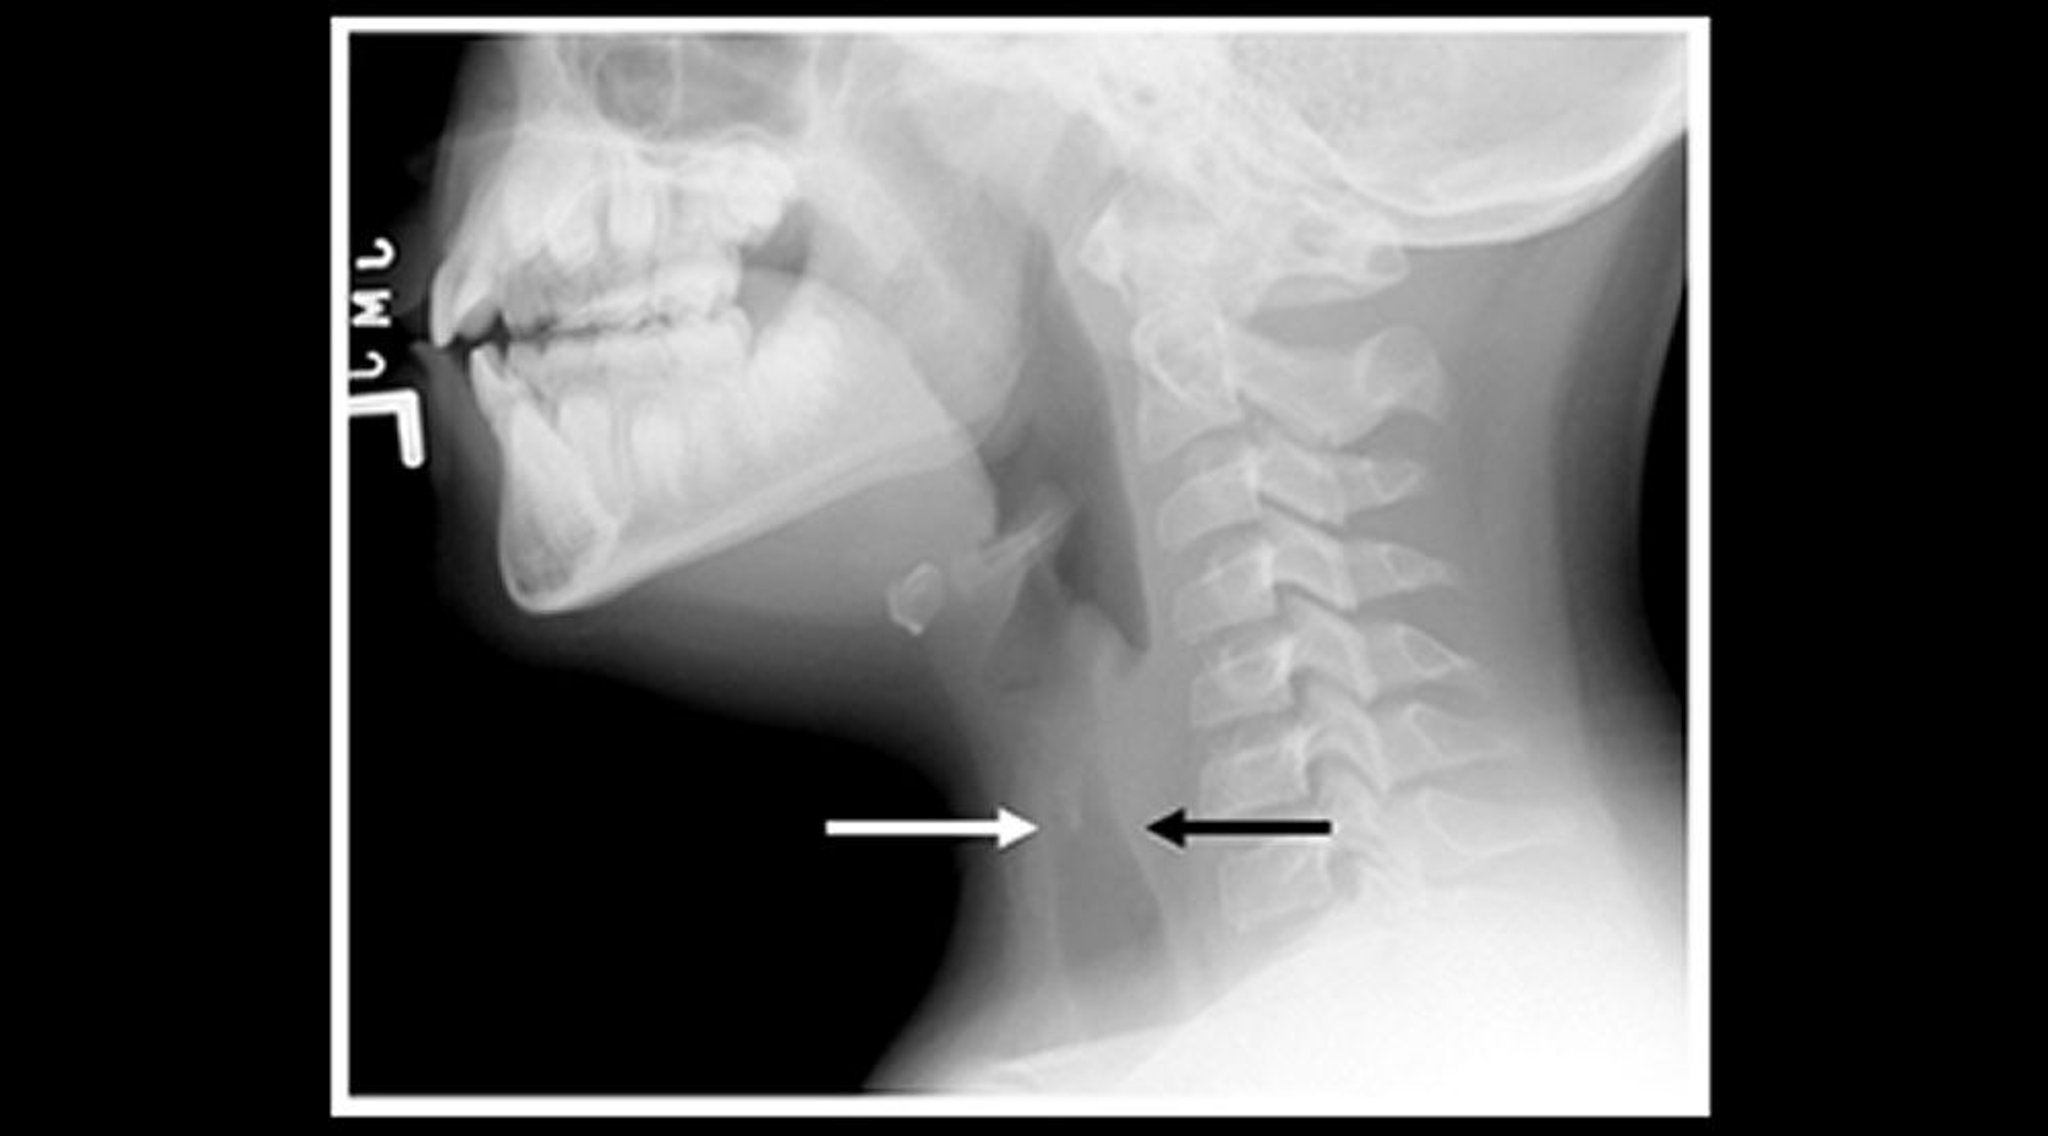

RX di un bambino con laringotracheobronchite acuta (proiezione sagittale)

Le radiografie del collo dei tessuti molli di un bambino con croup mostrano restringimento dell'ombra sottoglottica dell'aria tracheale (frecce) e dilatazione degli spazi aerei faringei.